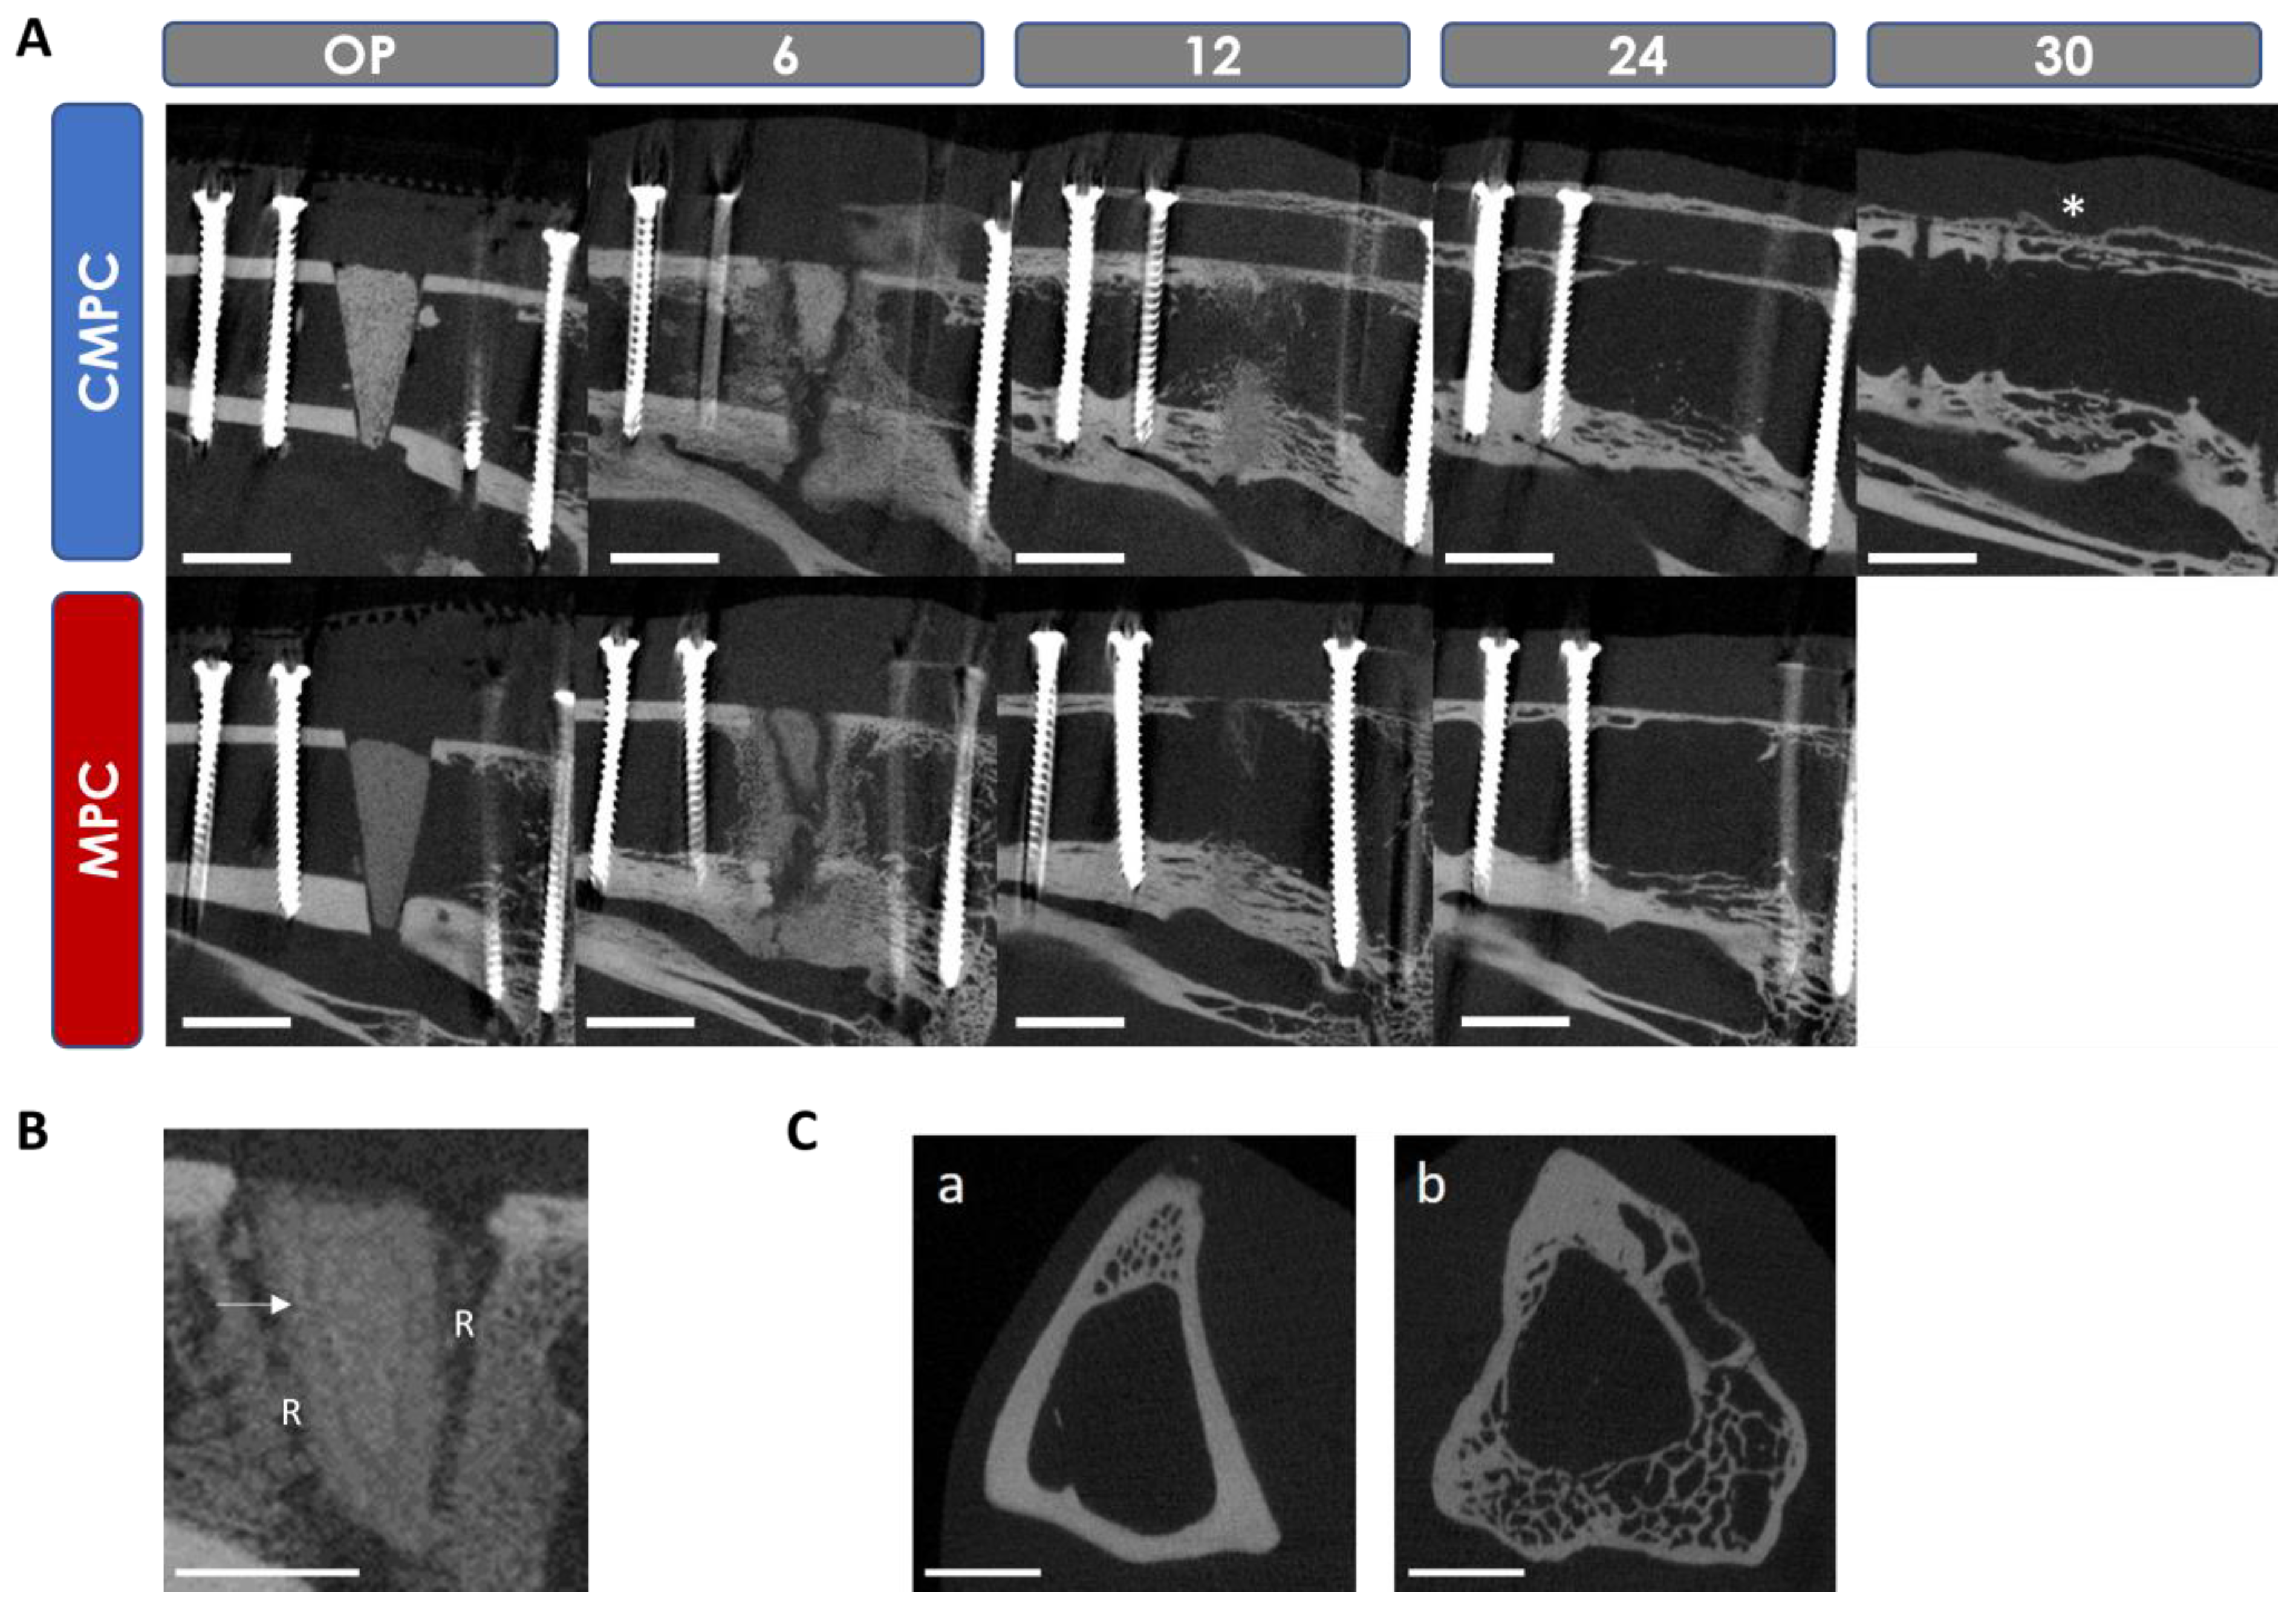

3.5. In Vivo µCT Examinations

3.5.1. Semi-Quantitative Evaluation of the Scans

3.5.2. Quantitative Evaluation of the Scans